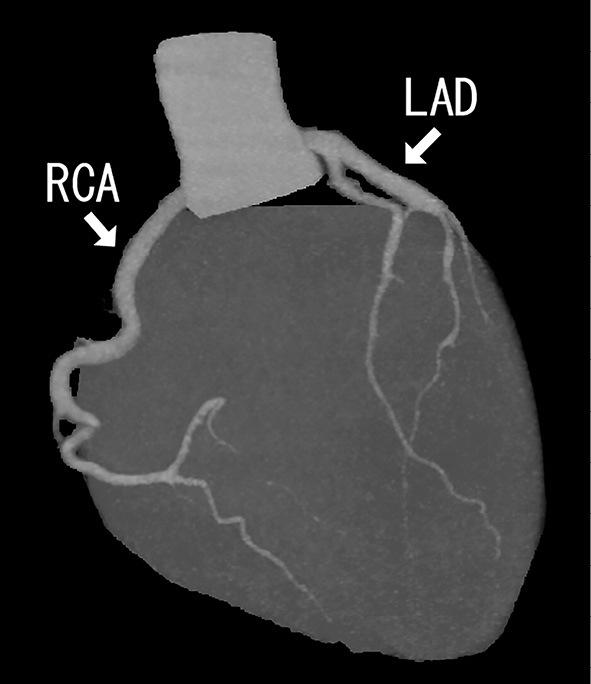

Kawasaki disease (KD) is an acute, self-limited vasculitis of unknown etiology that occurs predominantly in young children (≤5 years of age). We herein report the case of an 18-year-old Japanese man with a history of incomplete KD during infancy; later, despite an initial diagnosis of retropharyngeal abscess, he was ultimately diagnosed with retropharyngeal edema associated with recurrent KD. Adult-onset or recurrent KD is an uncommon event, and retropharyngeal edema is a rare manifestation of this disease. Internists should be aware of the possibility of KD that mimics a retropharyngeal abscess, even in adult patients.

川崎病(KD)是一种病因不明的急性自限性血管炎,主要发生于幼儿(≤5岁)。我们在此报告一例18岁日本男性病例,其婴儿期有不完全KD病史;后来,尽管最初诊断为咽后脓肿,但最终诊断为与复发性KD相关的咽后水肿。成人发病或复发性KD是一种罕见事件,咽后水肿是该疾病的一种罕见表现。内科医生应意识到即使在成年患者中,KD也有可能表现为类似咽后脓肿。